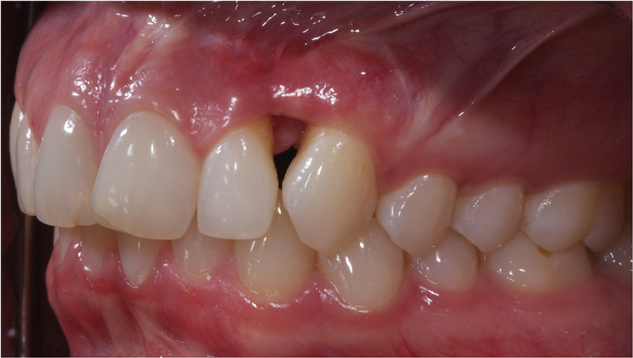

Figure 19 This patient presented with esthetic and functional concerns, but was reluctant to proceed with reconstructive dental treatment.

Figure 19

Figure 20 Intraoral examination revealed multiple concerns, including loss of vertical dimension, lack of posterior tooth support, and supra-eruption. There was also gingival asymmetry, and minimal zones of attached gingiva.

Figure 20

This patient previously presented with esthetic concerns but was reluctant to proceed with reconstructive dental treatment (Figure 19 and Figure 20). She had been monitored for several years and advised of the benefits of an interdisciplinary treatment plan including periodontal, dental implant, and prosthodontic therapy. The diagnosis included occlusal trauma, loss of vertical dimension, lack of posterior tooth support, and supra-eruption. There was also gingival asymmetry, lack of attached gingiva, lateral ridge defect for the mandibular left molar region, pneumatization of the maxillary right sinus, and alloy tattoo of the gingiva for the maxillary right bicuspids. Eventually the mandibular left second bicuspid, which was an abutment for a fixed partial denture, fractured, resulting in an abscess and significant bone loss localized to this abutment tooth (Figure 21). At this point, given the need for extraction and now more limited posterior chewing capability, the patient requested a comprehensive consultation and treatment plan for the reconstructive therapy she had previously elected to postpone.